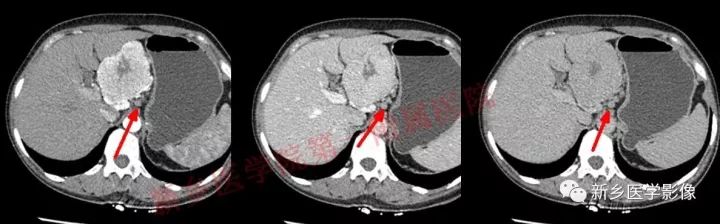

肝胃间胰腺前上方见类圆形肿块,边界较清,大小约8.2cm×4.6cm×5.9cm,密度欠均匀,内见点状钙化,增强呈不均匀明显强化,内见片状低密度灶无强化区,其下部与相邻胰腺分界不清,周围见粗大回流血管影回流至门静脉,病变左侧及腹膜后、胃壁小弯侧见数个卵圆形稍大淋巴结及结节影,部分呈环形强化。

GLNH高强化机制为透明血管型病灶内丰富的毛细血管增生和周边较多粗大的滋养动脉所致。

GLNH钙化较少,可见于5%~10%的病例,且仅见于局限型透明血管型。

GLNH另一个特征是瘤灶内极少伴有出血和坏死灶,尽管部分病例呈不均匀性强化,但瘤灶内的低密度影并非坏死灶。